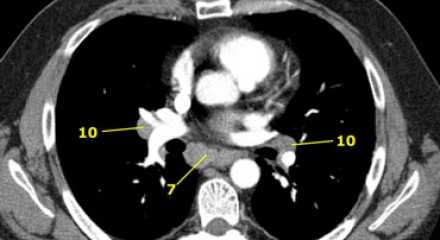

На левом изображении над уровнем легочного ствола представлены нижние паратрахеальные узлы слева и справа, так же здесь представлены узлы 3 и 5 групп.

Изображение слева выше уровня карины. Слева от трахеи 4L узлы. Обратите внимание что они расположены между легочным стволом и аортой, но не в аортопульмональном окне, потому что они лежат медиальнее артериальной связки. Лимфатические узлы латеральнее легочного ствола относятся к 5 группе.

7. Подкаринальные лимфатические узлы

Эти лимфатические узлы расположены ниже уровня бифуркации трахеи (карины), но не относятся к нижнедолевым бронху и артерии. Справа они располагаются каудальнее нижней стенки промежуточного бронха. Слева они располагаются каудальнее верхней стенки нижнедолевого бронха. Слева лимфатический узел 7 группы справа от пищевода.